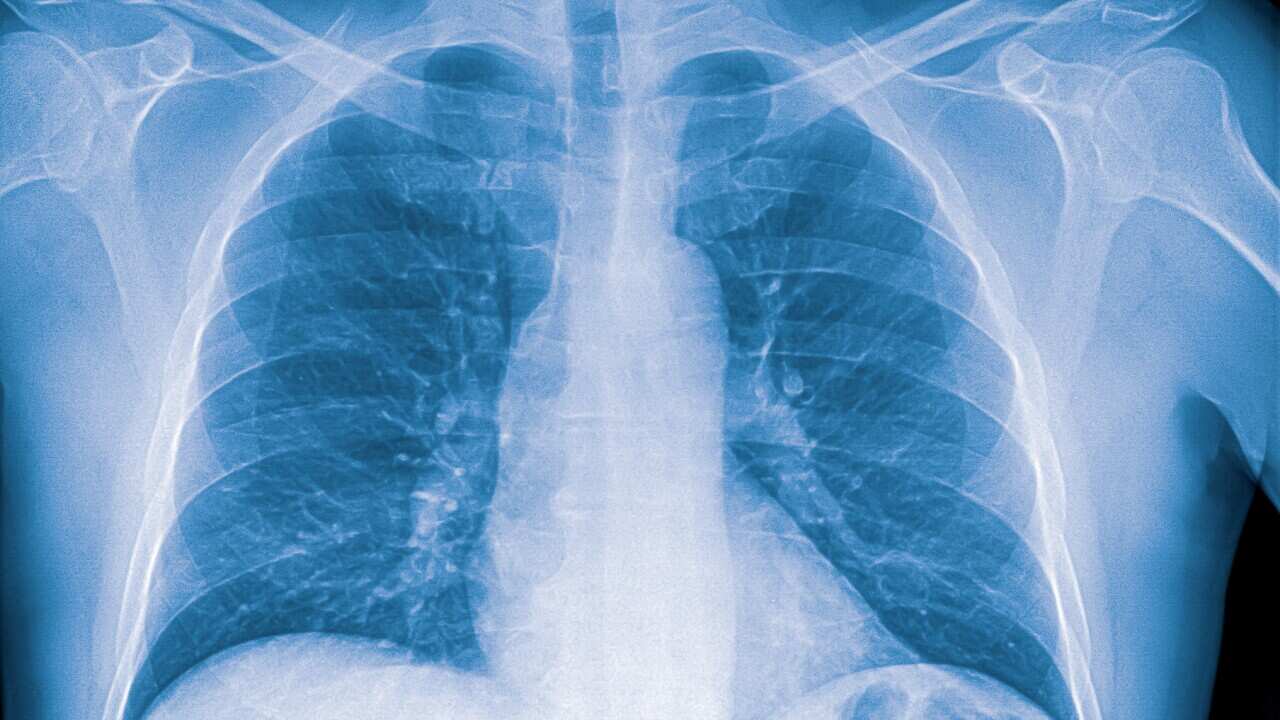

Ιδιαίτερα για τους ηλικιωμένους, μπορεί να υπάρξουν διάφορες συνέπειες, μετά από την πρόκληση πνευμονίας.

Ένα ενδεικτικό αποτέλεσμα… η αύξηση πρόκλησης καρδιακού ή εγκεφαλικού επεισοδίου, κατά τέσσερεις φορές!